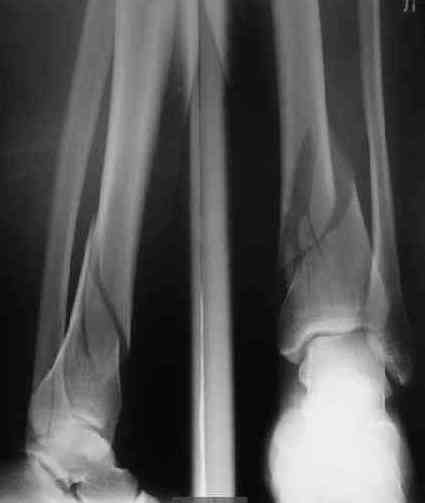

В приложении пример лечения аналогичного повреждения (плюс задний край).

Мы такие переломы закрыто штифтуем. Пластину больше смысла обсуждать, если требуется открытое восстановление суставной поверхности, костная пластика, в общем, если повреждение типа 33C3.

Выполнил MIPO предизогнутой метафизарной LCP